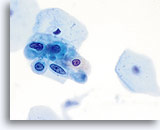

The ThinPrep Pap Test® minimizes the troublesome artifacts inherent in smear and spray fixation. This allows for

the nucleus to be adequately visualized facilitating a more definitive diagnosis. The epithelial cells that are generally incorporated in the ASC category are the mature squamous and squamous metaplastic cells exhibiting changes that are minimal and fall short of a diagnosis of LSIL or HSIL. The nuclei are slightly enlarged and this enlargement is compared to the normal entity of the same cell type. The nuclei may show slight nuclear membrane irregularities but are more often smooth. When dealing with the metaplastic component, one needs to make sure that the irregularities aren’t due to a vacuole(s) pushing the nucleus into the aberrant shape. The chromatin pattern is finely granular and evenly distributed. Chromocenters or nucleoli are generally inconspicuous or absent unless a reactive process is occurring in conjunction with the atypia at which point the differential diagnosis of reactive needs to be considered depending upon the presence or lack of the other criteria.

With either conventional or ThinPrep® slides, an ASC interpretation may arise from any of several different cellular changes, including but not limited to, squamous atypia, atypical squamous metaplasia, and atypical parakeratosis. The criteria for ASC on the ThinPrep Pap Test are as follows:

The images that follow are ThinPrep® Pap Test specimens that reasonably could be interpreted as reactive changes,

ASC-US, and LSIL.